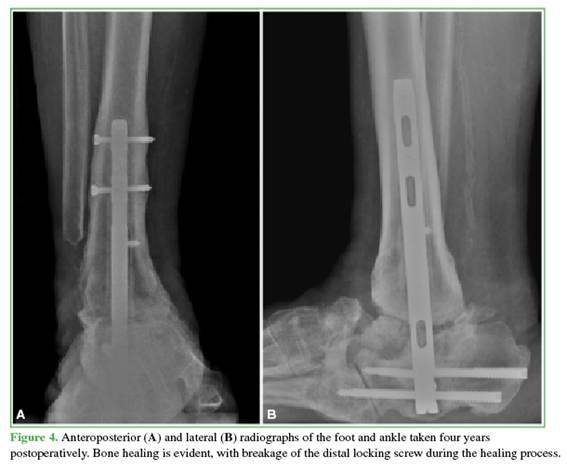

Three patients required revision arthrodesis: one due to implant failure following a fall and two due to nonunion (Figures 1 and 2). Revision procedures involved implant removal, debridement of the arthrodesis site, and re-arthrodesis using a new nail. All revision surgeries were preceded by optimization of metabolic parameters and comorbidities.

At the end of follow-up, seven patients had achieved stable healing of the TTC arthrodesis (Figures 3 and 4). Two developed fibrous healing, which allowed ambulation with orthotic support. One patient required a delayed revision and remains under follow-up. The median time to radiographic healing was 8.6 months (IQR 25-75%: 4.7–8.6).